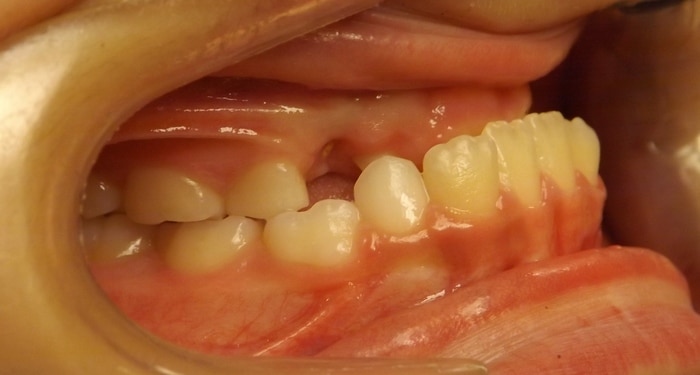

EMILY’S SMILE JOURNEY

Emily began with us as a Phase I patient and we just recently debanded her from Phase II. These progression photos show you that starting early allows us to not just straighten the teeth, but also change the patient’s jaw shape. Emily was a dedicated patient and did great with treatment. Her results speak volumes! We were able to correct her severe underbite and Class III skeletal imbalance without needing jaw surgery.